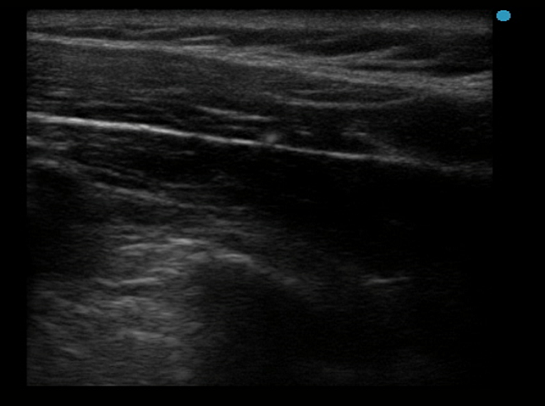

超音波画像診断装置、いわゆるエコー検査で筋肉と筋膜を見てその厚みを調べて凝っている筋肉とそうでない筋肉を比較、そこに鍼を打つとどうなるのか?

という研究でした。

今なら最安60万円ほどで揃えられるエコー装置が2千万円ほどしていた頃、初めてエコー装置で筋繊維が明瞭に見られるようになった時代ですので実験としては世界的にも初期だったはずです。

今でこそ「筋膜リリース」という言葉が巷で言われていますが、実際に筋膜の状態を観察したのもこの頃が初めだったと思います。

実験の結果としては、肥厚した筋膜に鍼が当たると筋膜と筋肉の厚みが薄くなるというものでした。